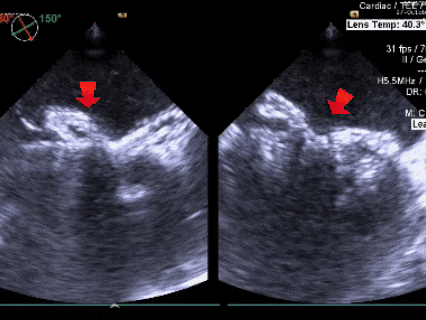

左盘展开

左盘展开后牵拉成型线使盘面成型,后撤鞘管和钢缆,使封堵器左盘贴靠房间隔

右盘展开

随后固定钢缆不动,回退鞘管,右盘展开